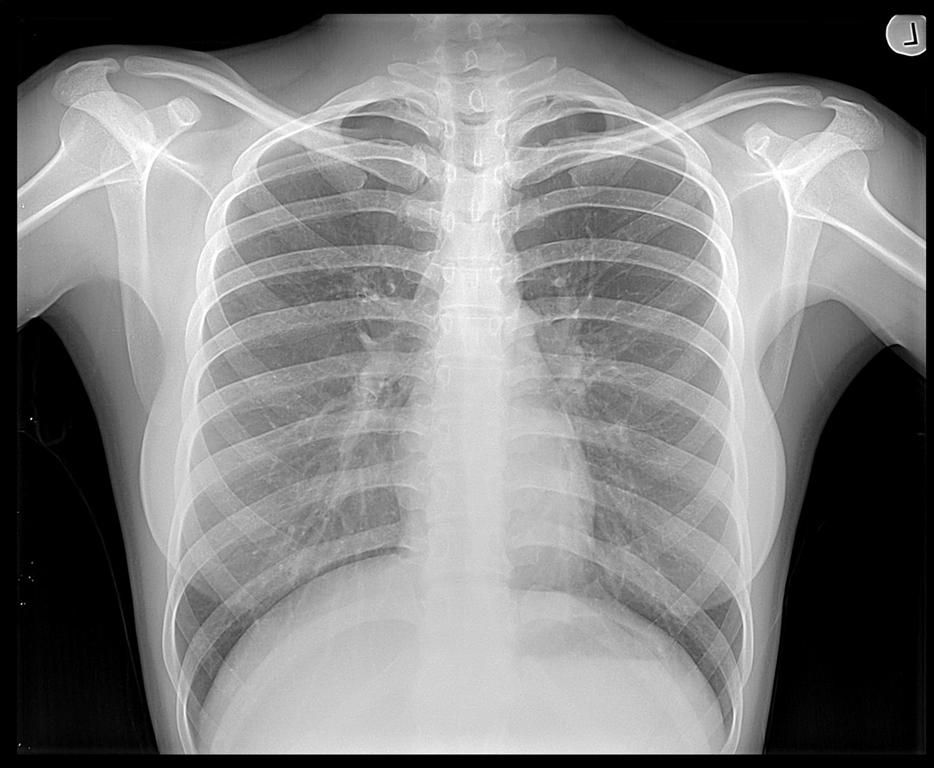

În ce condiții devin periculoase radiografiile

Razele X sunt radiaţii electromagnetice care permit vizualizarea clară a organelor pentru diagnosticarea unor afecţiuni. Beneficiile medicale sunt incontestabile, însă, în cantitate mare, aceste raze… Citește mai mult »În ce condiții devin periculoase radiografiile